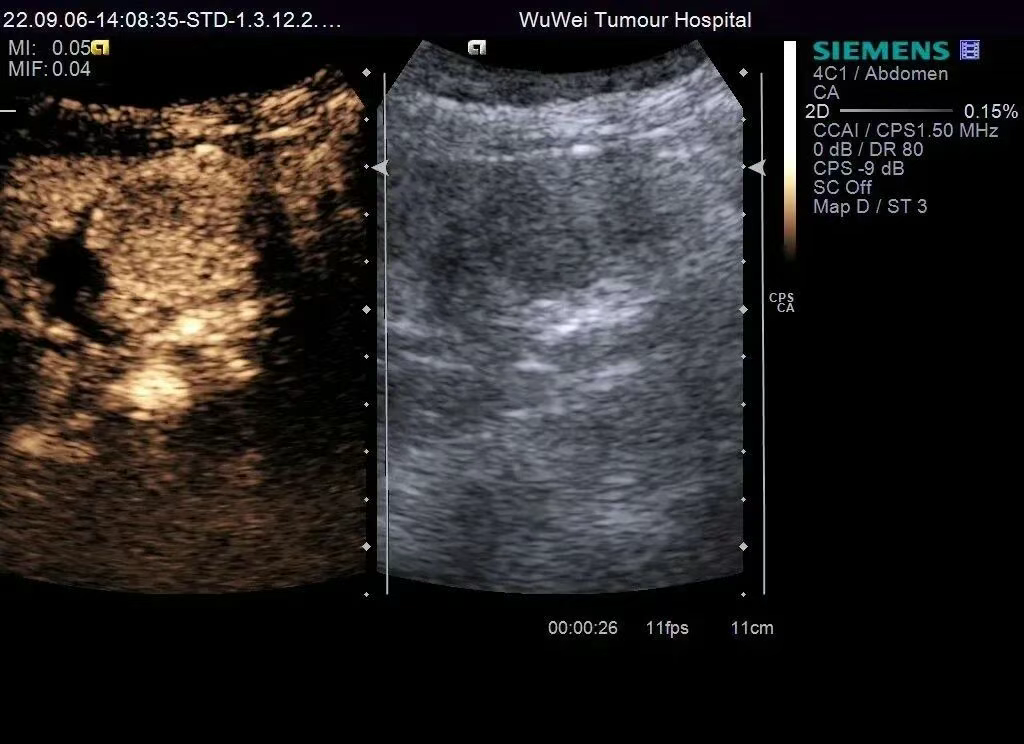

图4 超声造影灌注特征:胆囊底部低回声团块动脉期高于周围肝实质的均匀性高增强,20S达峰

图5 超声造影灌注特征:胆囊内病灶49s造影剂消退,门脉期呈不均匀低增强